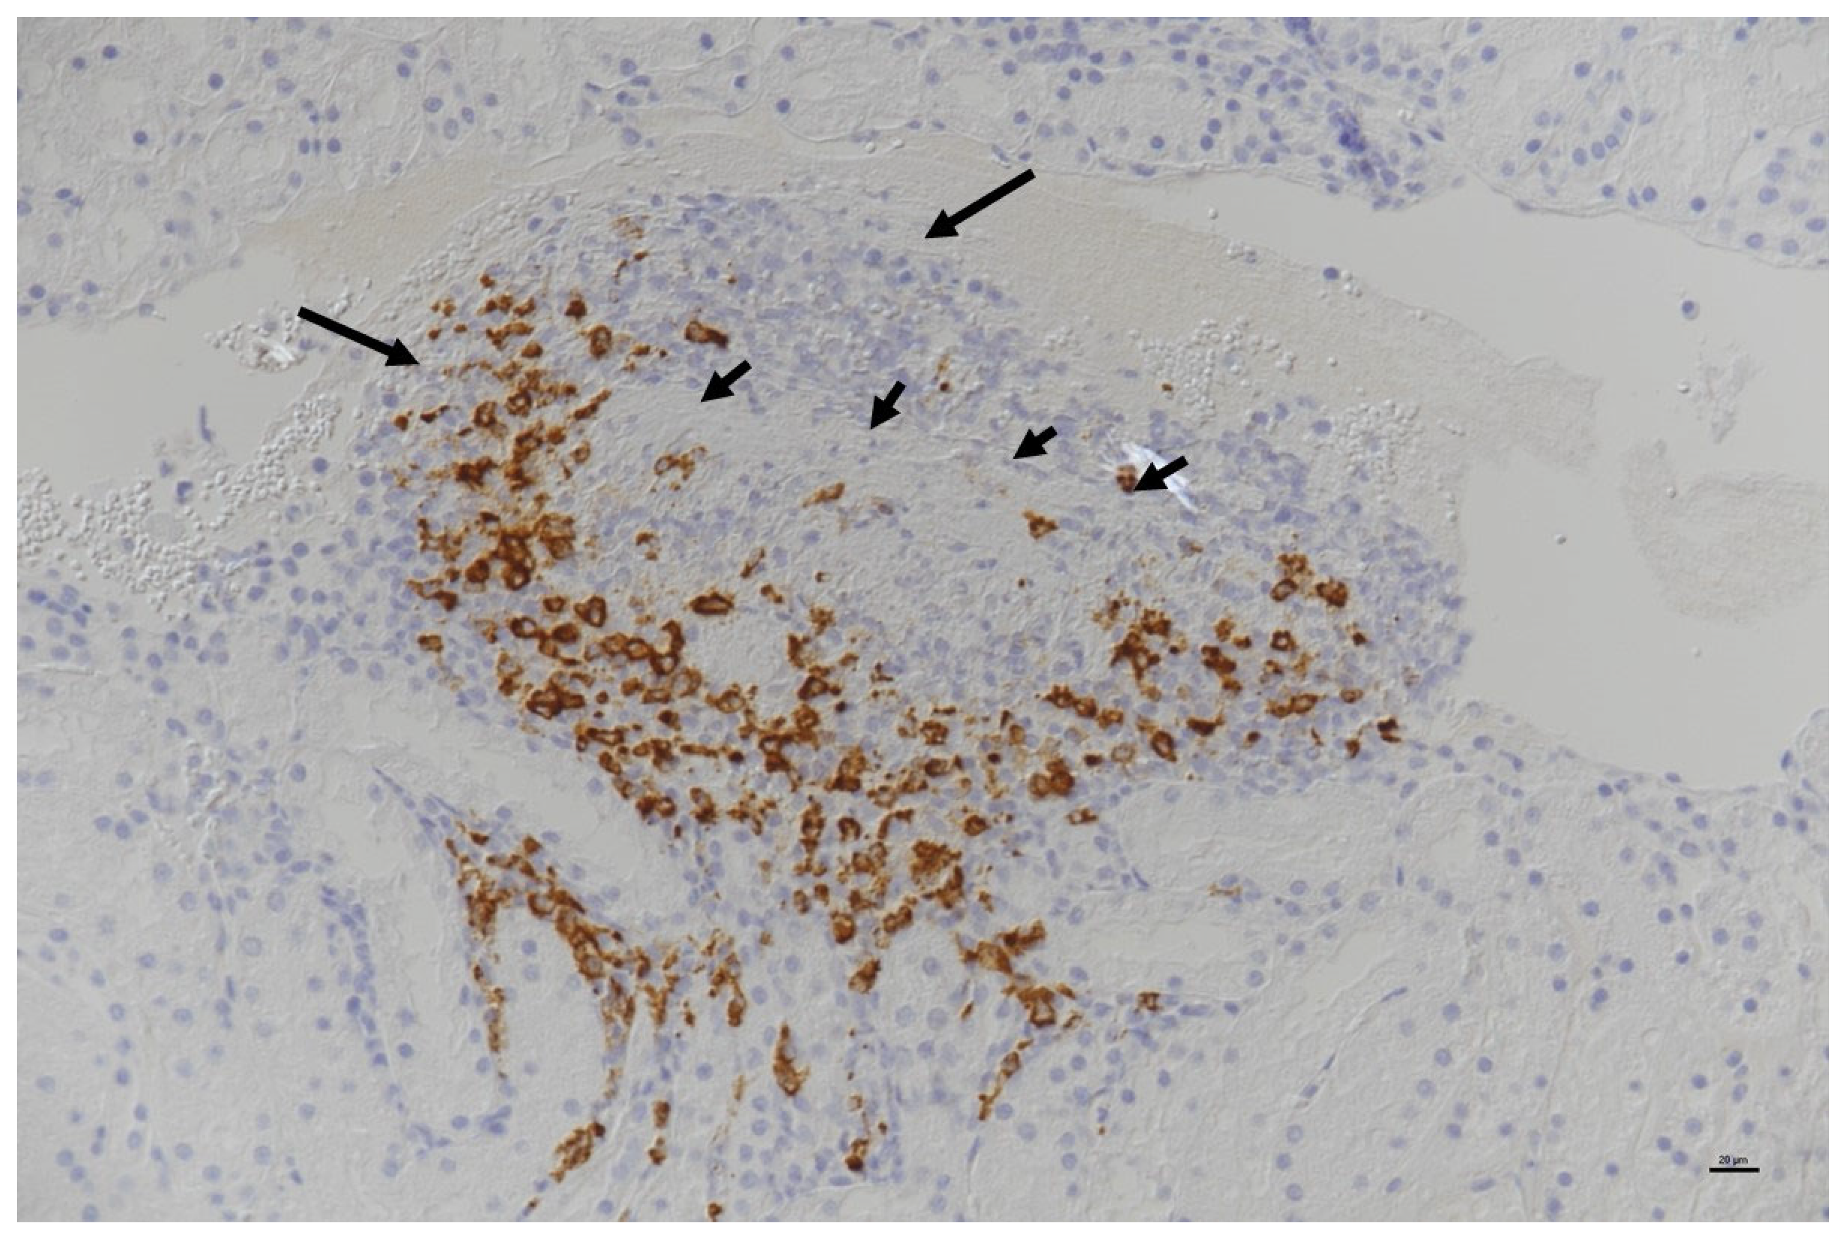

Histopathological Examination of Tissues with FCoV antigen Immunostaining

- Pyogranulomas on one or more serosal surfaces;

- Granulomas with or without necrotic areas;

- Lymphocytic and plasmacytic infiltrates in specific sites (e.g., band-like infiltrate in serosal surfaces, perivascular infiltrate in meninges and CNS);

- Granulomatous to necrotising vasculitis and fibrinous serositis.

| Summary of Section 7: Diagnosis of FIP; Section 7.5: Direct Detection of FCoV FCoV antigen detection by immunostaining Immunostaining exploits the binding of antibodies to host-cell-associated FCoV antigens, which are subsequently visualised by enzymatic or immunofluorescent reactions producing a colour change in a process called immunohistochemistry (IHC) on biopsies or immunocytochemistry (ICC) or immunofluorescence (IF) on cytology samples (such as effusion and fine-needle aspirate [FNA] sample smears). The histopathological and cytological changes associated with FIP are typically pyogranulomatous. Definitive diagnosis of FIP relies on consistent histopathological changes in affected tissues in addition to FCoV antigen immunostaining by IHC. Consistent cytological changes in affected tissues in addition to FCoV antigen immunostaining by ICC or IF is also highly supportive of a diagnosis. Although positive FCoV antigen immunostaining can usually be used to confirm the diagnosis, a negative result does not exclude FIP as FCoV antigens can be variably distributed within lesions and might not be detected in all samples prepared from FIP-affected tissues or samples (e.g., if an effusion is cell-poor and/or the FCoV antigen is masked by FCoV antibodies in the effusion). It is important for clinicians to be aware of variations in immunostaining techniques and to be familiar with the specificity of the methodology employed by their local laboratory, as well as confirmation of the inclusion of negative controls in testing, when interpreting positive results. Differential diagnoses for pyogranulomatous inflammation include other infections (mycobacteria, toxoplasmosis, actinomyces, nocardia, rhodococcus, bartonella, pseudomonas and fungi) as well as idiopathic sterile pyogranulomatous disease. The sample sites most likely to be useful are those that are affected by the FIP disease, and inference of this can be gained from the clinical signs as well as results of diagnostic testing (e.g., ascites, neurological signs, imaging results, pyogranulomatous inflammation on FNA cytology). Biopsy samples of affected tissues (e.g., liver, kidney, spleen, mesenteric lymph nodes) can be collected by laparotomy, laparoscopy or ultrasound-guided tru-cut for histopathology and immunostaining, whereas effusions, FNAs (e.g., of mesenteric lymph nodes), cerebrospinal fluid (CSF) and aqueous humour samples can be collected for cytology and immunostaining. It is wise to consult the diagnostic laboratory before submitting samples for ICC or IF as their preferences for how samples should be prepared before sending vary. FCoV RNA detection by reverse-transcriptase polymerase chain reaction (RT-PCR) FCoV RT-PCR assays can be used to detect FCoV RNA in blood, effusion, tissue (including samples obtained by FNAs), CSF, or aqueous humour samples. The RT-PCR assays used should be quantitative and report the FCoV load (amount) present in the analysed sample. The load is helpful because the systemic FCoV infection that can occur in healthy cats and cats without FIP have lower FCoV viral loads than in cats with FIP. Thus, a positive FCoV RT-PCR result on a sample is not totally specific for FIP, but positive results with a high FCoV load on samples from cats with signs consistent with FIP are very supportive of a diagnosis of FIP, and often this is adequate evidence upon which to start a cat with antiviral FIP treatment. However, a negative result cannot rule out a diagnosis of FIP since the levels of FCoV in samples can be too low or have too variable a distribution (and thus not present in the sample analysed) to be detectable by PCR. It is wise to consult the diagnostic laboratory before submitting samples for RT-PCR, as their preferences for how samples should be prepared before sending vary (e.g., centrifugation of effusions, preservation advice). Recent studies using RT-PCR on blood samples have shown more promising results than previously, with high levels of FCoV RNA detectable, suggesting that blood samples could be revisited as a diagnostic sample to support a diagnosis of FIP. RT-PCR analysis of effusion samples in cats with FIP is often positive (72–100% of samples) for FCoV RNA, and cats without FIP are usually RT-PCR-negative, and the presence of FCoV RNA, particularly in high levels, in an effusion that also has cytological and biochemical features suggestive of FIP, is highly supportive of a diagnosis of FIP. Whilst tissue biopsy samples obtained from affected tissues in cats with FIP usually show high levels of FCoV RNA in them, as determined by RT-PCR, such samples, if collected, should ideally be submitted for histopathology and IHC, as this allows for a definitive diagnosis of FIP. FNAs are a good sample type for FCoV RT-PCR, with the advantage of relatively easy collection. The sample site should be guided by where pathology is likely based on clinical signs and other diagnostic investigations, but promising results on FNAs collected from mesenteric lymph nodes from cats with FIP that did not have effusions have been obtained. CSF and aqueous humour FCoV RT-PCR in cats with neurological signs or ocular signs, respectively, can also be helpful. RT-PCR on faecal samples is only useful to identify cats shedding FCoV for the management of FCoV in multi-cat households. Faecal RT-PCR is not useful for the diagnosis of FIP as many healthy cats without FIP shed FCoV. Characterising FCoV spike (S)-gene mutations following positive RT-PCR for FCoV RNA Following the detection of FCoV RNA in a sample by RT-PCR, varied molecular techniques (e.g., pyrosequencing and Sanger sequencing often used in research, or methods that detect and quantify specific FCoV mutation sequences, such as the commercially available allelic discrimination assay) can be used to derive S-gene sequence data for the FCoV present. Such techniques are only successful at determining the FCoV sequence present when high loads of FCoV RNA are present, so successful S-gene-mutation analysis at least suggests that the sample contained high levels of FCoV RNA, which is highly supportive of a diagnosis of FIP. However, research has shown great variability in results when detecting S-gene mutations using the different methods, making it difficult to rely on S-gene-mutation analysis as being confirmative for FIP, especially when the commercially available allelic discrimination assay is used. |